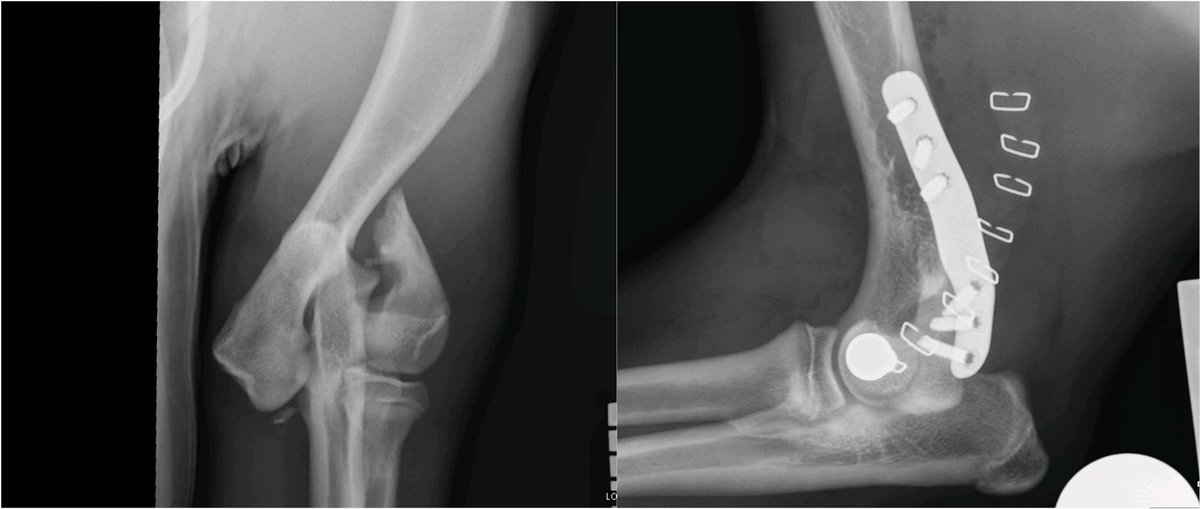

The Lateral Epicondylar Anatomical Plate from Fusion Implants is a great LEAP forwards. It makes repairing these fractures super-satisfying and provides a reliable locking plate construct for these dogs.

The Lateral Epicondylar Anatomical Plate from <a href="/FusionImplants/">Fusion Implants</a> is a great LEAP forwards. It makes repairing these fractures super-satisfying and provides a reliable locking plate construct for these dogs.

Meet Mac and his unusual, spiral dicondylar fracture. Kept me and the fantastic ⁦@CGVetSpecialist⁩ team busy today. Thank heavens for the ⁦Fusion Implants⁩ LEAP to save a bit of time@near the end.

Meet Mac and his unusual, spiral dicondylar fracture. Kept me and the fantastic ⁦@CGVetSpecialist⁩ team busy today. Thank heavens for the ⁦<a href="/FusionImplants/">Fusion Implants</a>⁩ LEAP to save a bit of time@near the end.